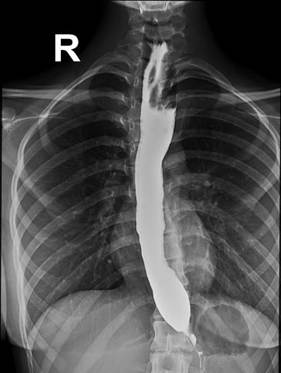

Q.5

Clinical Question:

Following a building collapse, a male patient was brought to the emergency department with a copious amount of debris in the mouth, making endotracheal intubation impossible. The emergency procedure shown in the image was performed. Which of the following statements regarding this procedure is true?

Options:

- It is used for effective ventilation for up to 6 hours

- It is used to measure central venous pressure

- It should be followed by a tracheostomy

- The work of breathing is more than with bag-and-mask ventilation

Correct Answer: C) It should be followed by a tracheostomy